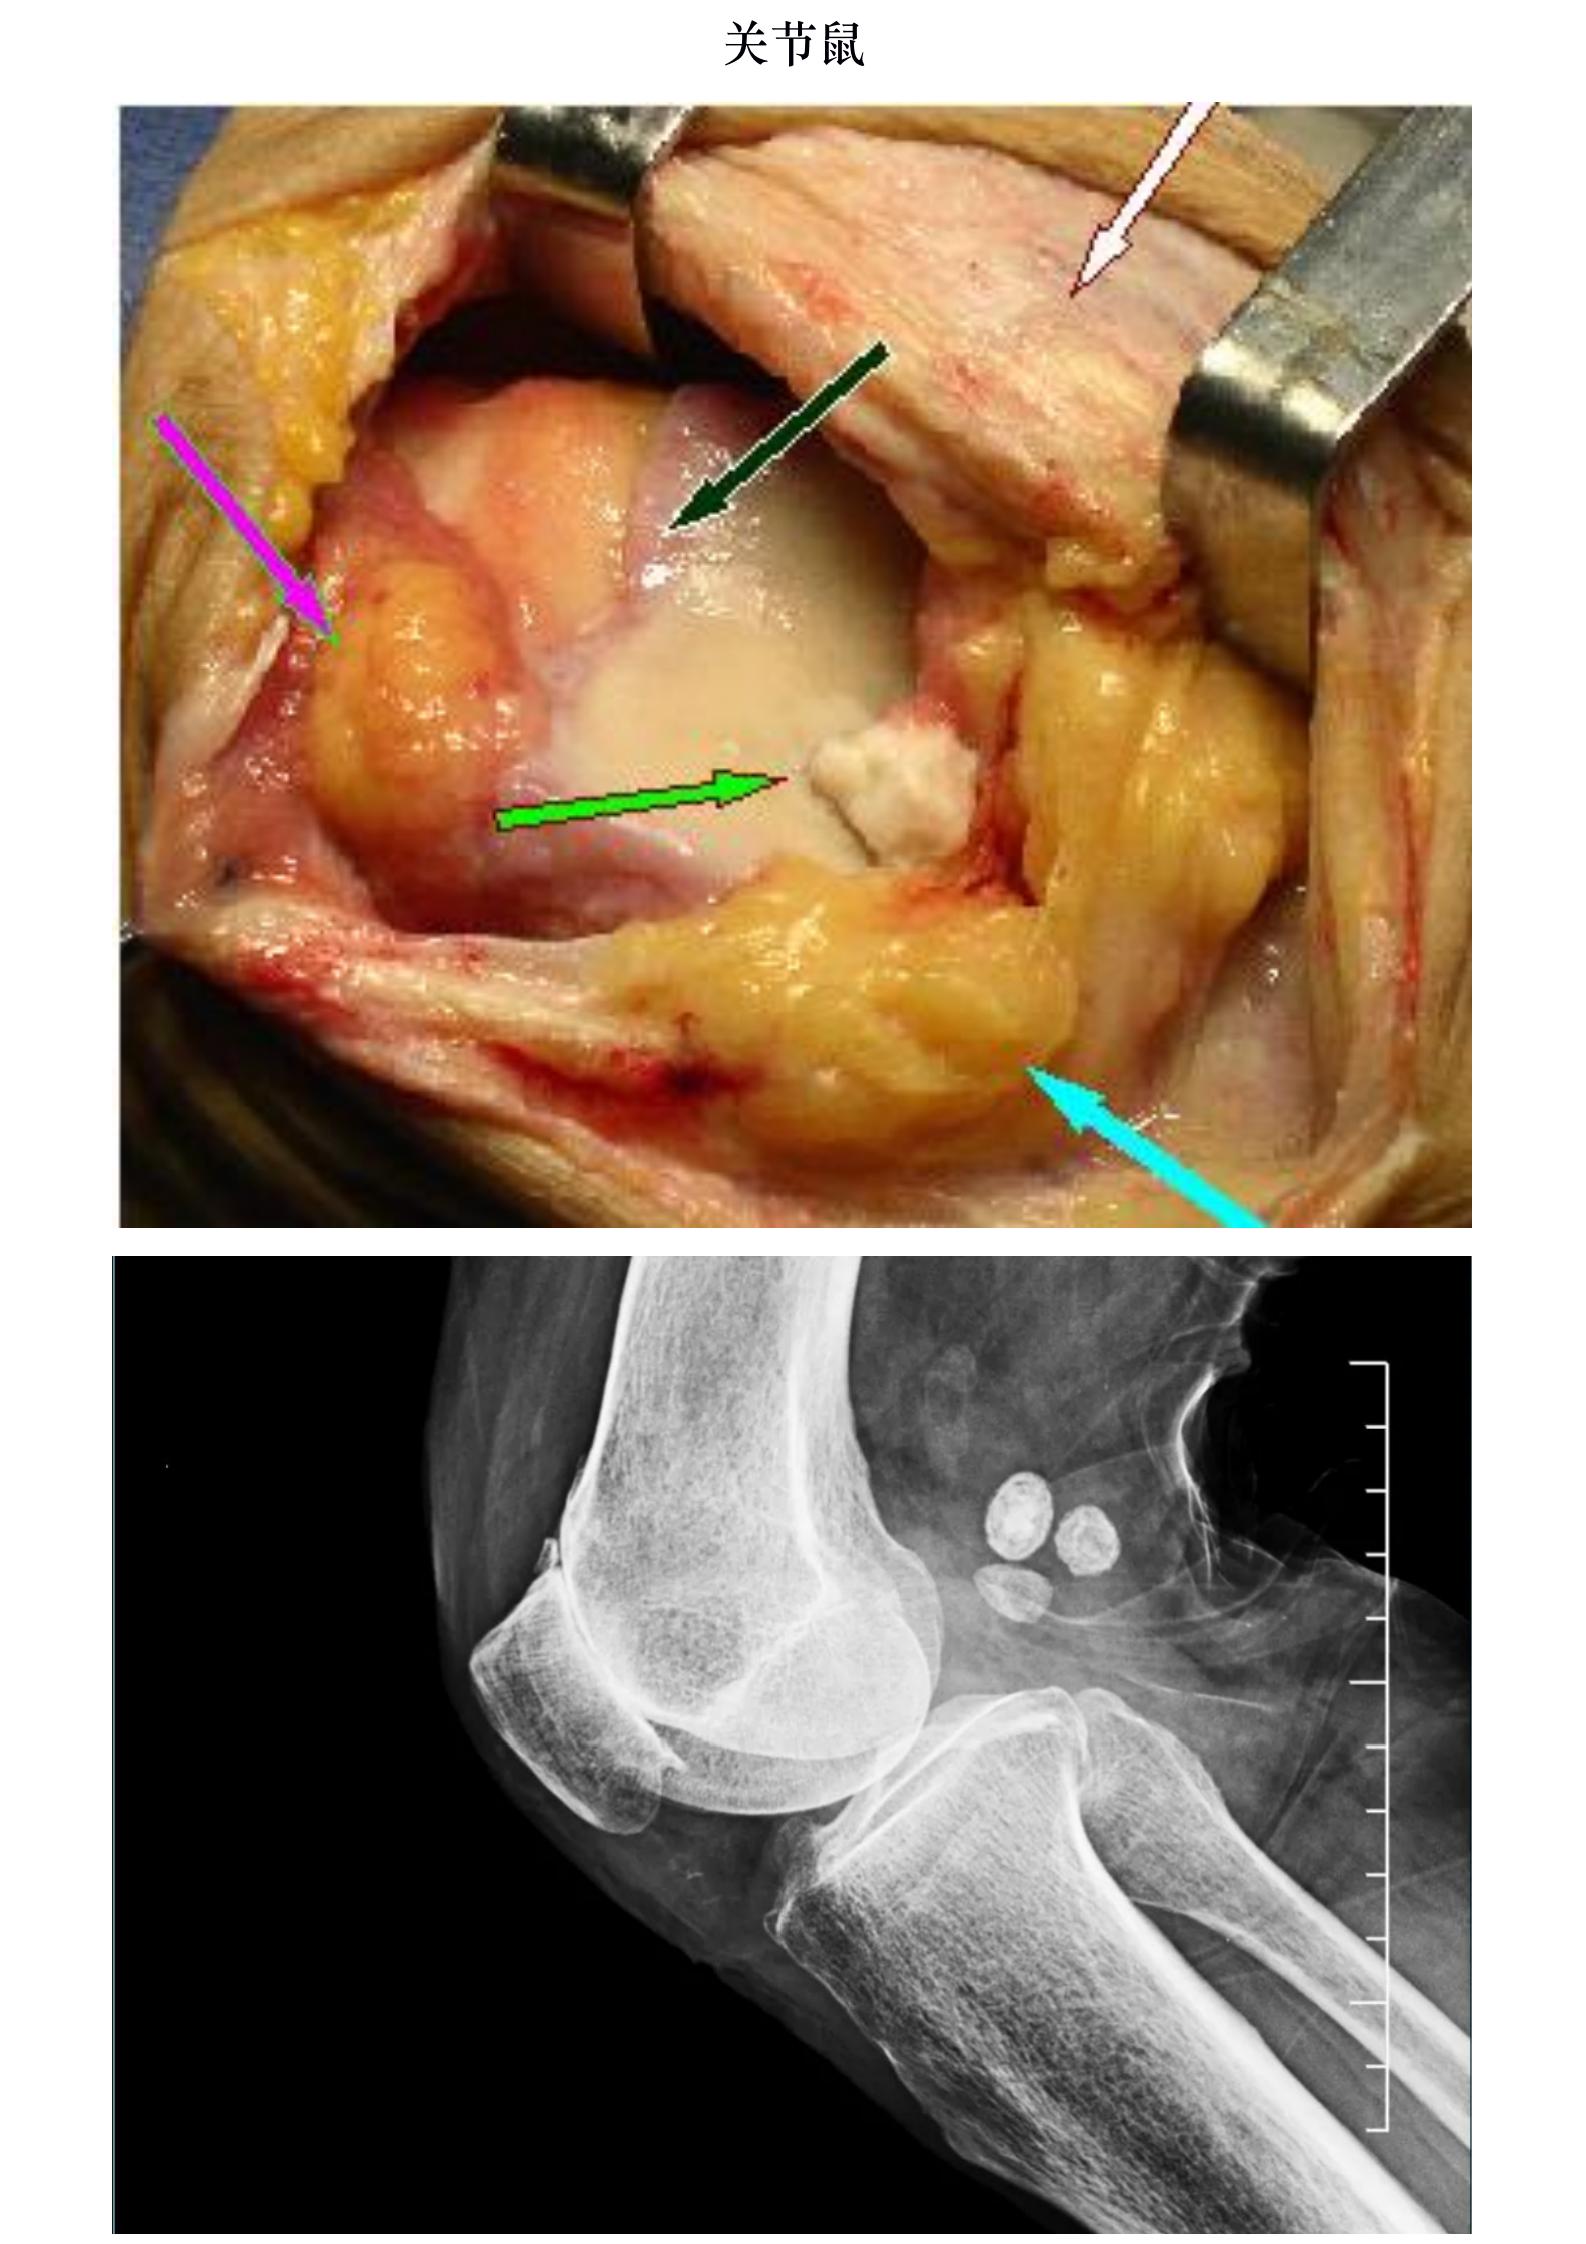

关节鼠